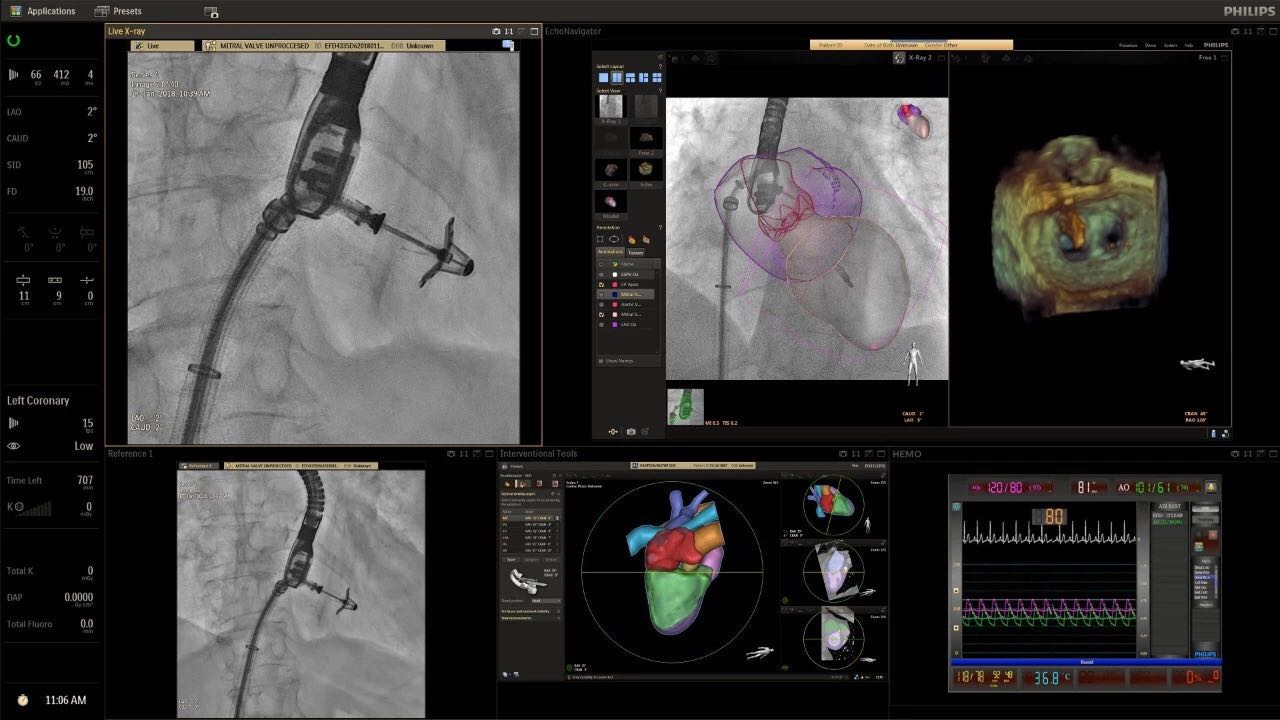

在日益復(fù)雜的干預(yù)期間,臨床醫(yī)生需要快速、輕松地可視化關(guān)鍵解剖結(jié)構(gòu)并確定手術(shù)過程中患者的變化。2019年1月17日,飛利浦宣布推出采用FlexArm的Azurion 7 C20,旨在提高圖像引導(dǎo)程序的定位靈活性。

帶有FlexArm的Azurion 7 C20 包含一系列創(chuàng)新技術(shù),使臨床醫(yī)生可以更輕松地在整個(gè)患者身上進(jìn)行二維和三維成像。當(dāng)臨床醫(yī)生移動(dòng)系統(tǒng)時(shí),圖像光束自動(dòng)保持與患者的對準(zhǔn),允許更一致的可視化并使他們能夠?qū)⒆⒁饬性谥委熒稀?/span>

飛利浦表示,采用FlexArm設(shè)計(jì)的Azurion 7 C20可提供卓越的靈活性和直觀的控制。該系統(tǒng)由智能運(yùn)動(dòng)引擎驅(qū)動(dòng),可在八個(gè)不同的軸上移動(dòng),所有這些軸均由其單個(gè)“Axsys”控制器控制。臨床醫(yī)生的模擬測試表明,該系統(tǒng)有可能顯著減少患者,工作人員和設(shè)備的重新定位,從而改善微創(chuàng)手術(shù)的可及性,包括通過患者手腕進(jìn)入身體的手術(shù)(橈動(dòng)脈入路),并降低患者的風(fēng)險(xiǎn)。無意中拔出電線和管子,以及節(jié)省大量時(shí)間。該系統(tǒng)非常適合混合手術(shù)室(OR),可滿足一個(gè)房間內(nèi)的多種專業(yè)需求,例如手術(shù)和血管內(nèi)手術(shù)的組合。

(FlexArm在不少于8軸的情況下旋轉(zhuǎn),從而創(chuàng)建幾乎無限的靈活性來執(zhí)行成像,從頭部到腳部在左側(cè)和右側(cè)進(jìn)行2D和3D可視化。圖像光束保持與患者對齊,允許在旋轉(zhuǎn)或角度期間更好地可視化解剖結(jié)構(gòu)。使用Axsys運(yùn)動(dòng)控制系統(tǒng)輕松操作支架。)